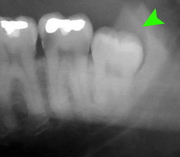

Wisdom teeth likely become impacted because of a mismatch between the size of the teeth and the size of the jaw. Impacted wisdom teeth are classified by their direction of impaction, their depth compared to the biting surface of adjacent teeth and the amount of the tooth's crown that extends through gum tissue or bone. Impacted wisdom teeth can also be classified by the presence or absence of symptoms and disease. Screening for the presence of wisdom teeth often begins in late adolescence when a partially developed tooth may become impacted. Screening commonly includes clinical examination as well as x-rays such as panoramic radiographs.

If the tooth cannot be assessed with clinical exam alone, the diagnosis is made using either a panoramic radiograph or cone-beam CT. Where unerupted wisdom teeth still have eruption potential several predictors are used to determine the chance of the teeth becoming impacted. The ratio of space between the tooth crown length and the amount of space available, the angle of the teeth compared to the other teeth are the two most commonly used predictors, with the space ratio being the most accurate. Despite the capacity for movement into early adulthood, the likelihood that the tooth will become impacted can be predicted when the ratio of space available to the length of the crown of the tooth is under 1.[3]:141